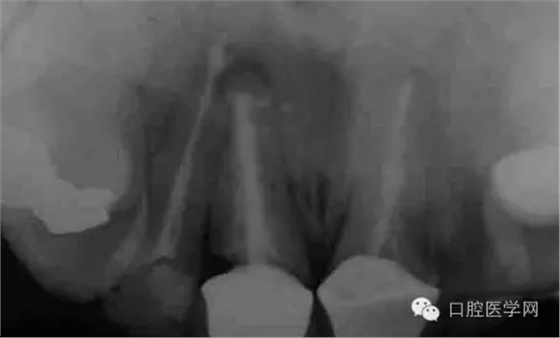

圖1 X線顯示上11根尖息肉陰影

圖12 術(shù)后X片顯示